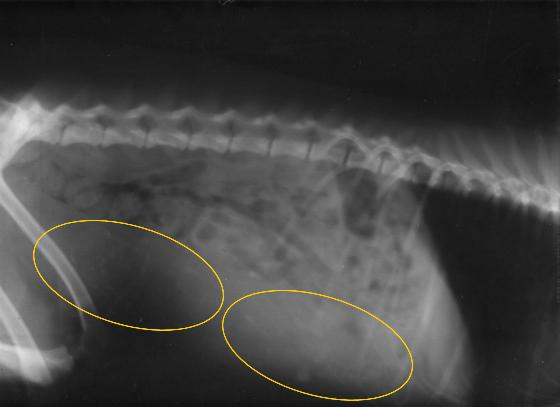

出産に向けて【レントゲン】

今日は会社が休みなので、少し早めですが珊瑚をレントゲン確認に連れて行きました。

結果:なんと3頭いる事を確認! 体温は39.4℃

画像ではわかり難いのですが・・・3頭目の仔は他の2頭と比較すると、骨の写りが薄いので、まだ微妙らしい・・・順調に成長してくれれば良いのですが、最悪の結果もあると・・・珊瑚は相変わらず食事が進まないのですが、体重は+200gで順調との事でもう少し体重が有っても良いと言って頂けたので、胎児の成長にを助ける為にも食事を更にバランス良い形で骨の成長を助ける物へと移行させます!

新たな生命の発見、せっかく授かった命です。頑張れー!!!

出来る限りの事をしてやりたい。